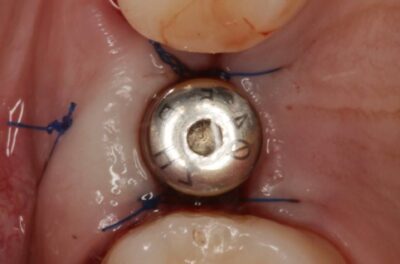

Специализация: терапия(эндодонтия), ортопедия, имплантология.